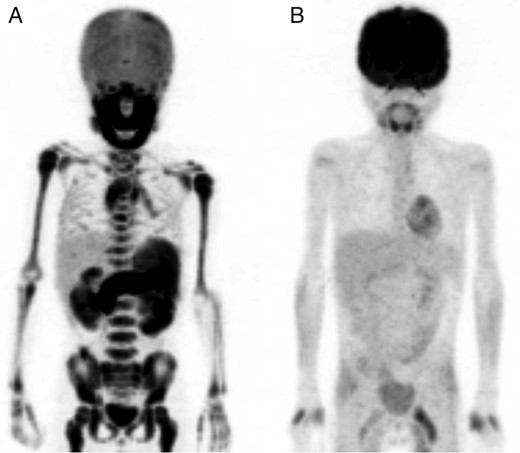

The patient had additional examinations at the department. Bone marrow aspiration from the ilium showed a diffuse monotonous pattern of infiltration by medium-sized cells with round nuclei and basophilic cytoplasm containing vacuoles. Immunophenotype analysis was negative for CD3, TdT, MPO, MIC2 and BCL2 and positive for CD10, CD20, CD79a, c-myc and Ki67 (Fig. 2, data not shown partially). Chromosome banding by fluorescence in situ hybridization (FISH) showed translocations t (8;14)(q24;q32) (data not shown). Positron emission tomography/CT (PET/CT) showed diffusely increased 18F-fluorodeoxyglucose uptake in bone (Fig. 3A). Based on the physical examination, immunohistochemical staining, genetic analysis and imaging findings, the final diagnosis was Stage IV Burkitt's leukaemia.

PET/CT image. (A) PET/CT image showing increased 18F-fluorodeoxyglucose uptake in the whole skeleton. (B) PET/CT image after two course of chemotherapy showing complete remission of 18F-fluorodeoxyglucose uptake.

The patient underwent chemotherapy based on the Japanese Paediatric Leukaemia/Lymphoma Study Group B-NHL03 protocol [2]. After one course of chemotherapy, CT images showed partial reduction in the size of the masses in the maxillary sinuses (Fig. 1B). Following two courses of chemotherapy, complete remission of abnormal uptake in the entire body was confirmed by PET/CT imaging (Fig. 3B). To date, the patient is alive and under regular surveillance by the Department of Paediatric Haematology and Oncology.